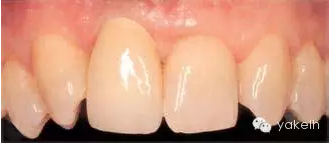

患者前牙3個(gè)單位的固定橋修復(fù),UR1和UL2為種植體(圖.7),存在美學(xué)問題。為了糾正修復(fù)位點(diǎn)的軟組織缺陷,修復(fù)體選用粉色瓷層,這樣可以調(diào)整牙齒的大小和外形。但是該病例左上兩種植體頸部金屬外露,周圍黏膜存在炎癥,同時(shí)種植體周圍軟組織下方透出灰色。

圖.7 修復(fù)體選用粉色齦層糾正了軟組織缺陷,種植體頸部暴露影響美觀效果。